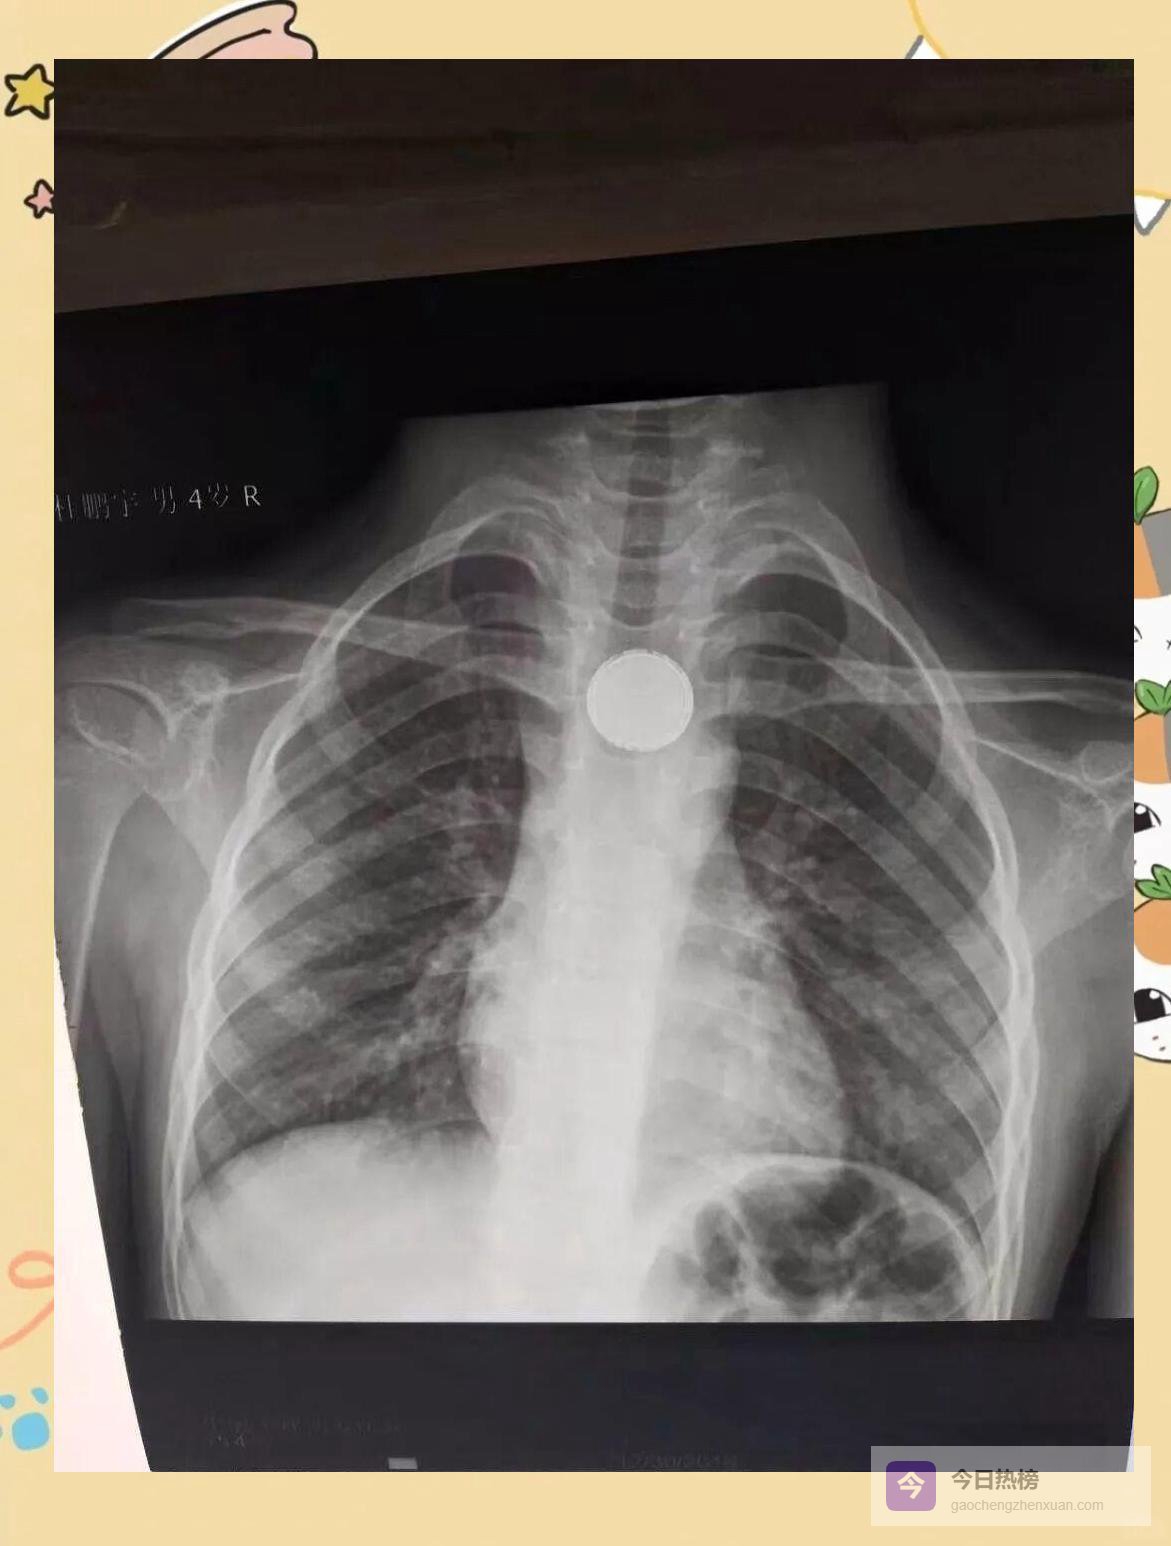

03消化科:异物急诊“绿色通道”,五场惊险同步上演

3.1 ❒ 假期首日,异物榜单刷新仅元旦上午, “绿色通道”就紧急介入5例吞食异物患儿:不到1岁的婴儿误吞纽扣电池,7岁女孩枣核卡喉,还有指甲刀、硬币……每一例都可能演变为消化道穿孔或化学性灼伤。

3.2 ❒ “有惊无险”背后的高强度协作 内镜中心、麻醉科、手术室无缝衔接:钳取、剥离、探查,每一分钟都在与腐蚀性损伤赛跑。孩子哭声停歇,家长泪光闪动,一句“谢谢”被反复说出,成了医护最动听的“新年彩蛋”。